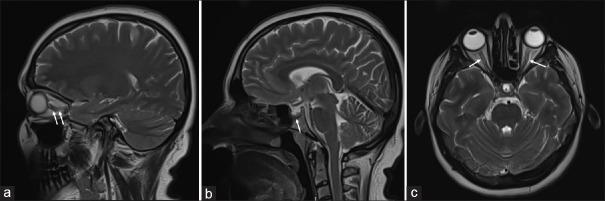

Stapes reflex test is a method of evaluating the involuntary muscle contraction of the stapedius muscle in response to a high-intensity sound stimulus. The formation of this reflex involves the intact function of the 7 nerve, brain stem, 8 nerve, and middle ear. Due to ease of administration and information yielded, the stapedial reflex is considered one of the most powerful differential diagnostic audiological procedures. Numerous studies have remarked on the fluid communication between the intracochlear and intracranial spaces through the cochlear aqueduct. Currently, the potential significance of a noninvasive audiological technique in the discrimination of raised intracranial pressure constitutes a crucial topic of interest.

We have performed the pre-LP and post-LP detailed otorhinolaryngological investigations, including the detailed inspection, audiometric testing, tympanometry, and stapedial reflex in a total of four consecutive patients with IIH.

We found that the stapedial reflex was bilateral absent initially in two of the patients. However, the second stapedial reflex investigations after LP showed reversal of the reflex responses in both of the patients.